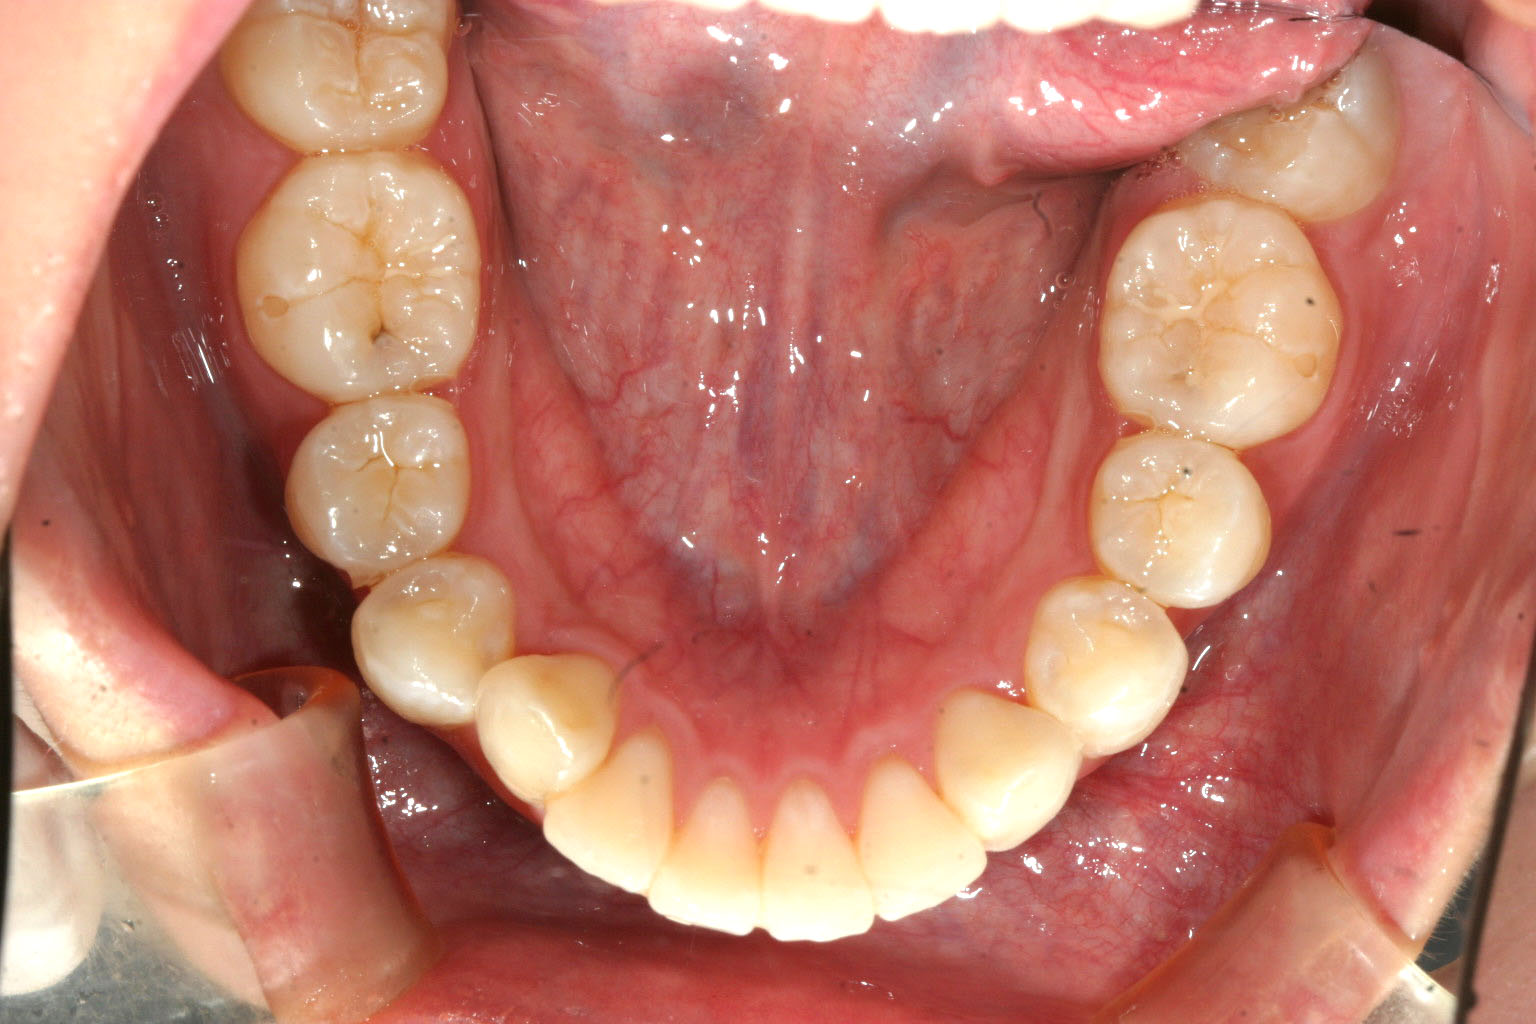

下顎もこうして歯列だけ見るとほぼ綺麗な状態です。

左右小臼歯の抜歯を行い矯正行いました。

下顎はそのまま歯列を整えました。